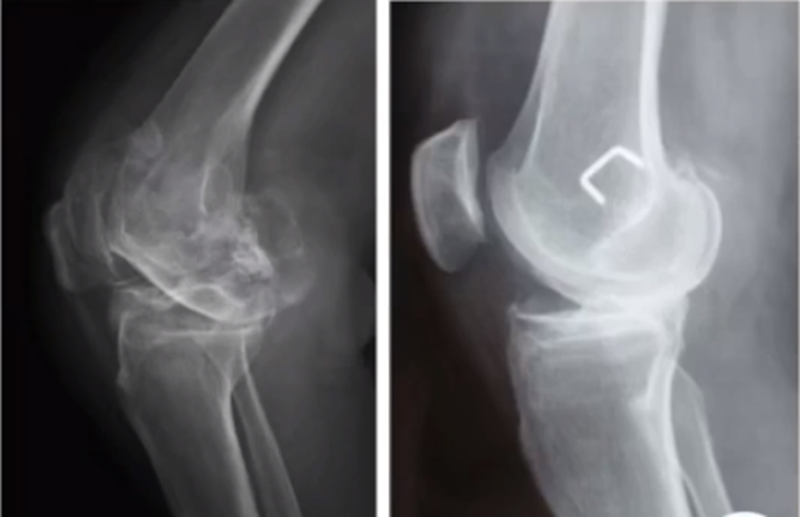

三、单髁置换的适应证——标准侧位片

标准侧位片,内外髁完全重叠,胫骨平台也一样,如果检查不标准,X线片结果会影响判断。

侧位片可以显示胫骨平台磨损部位,在判断前交叉韧带功能是否完好方面有重要意义。当磨损部位在前方或中前方,没有延伸到胫骨平台后缘时,说明前交叉韧带功能正常;当磨损部位延伸到胫骨平台后方,甚至引起后方半脱位状态时,说明前交叉韧带功能缺失或损害,此时不适合做单髁。

AMOA的侧位X线表现

ACL功能完好是单髁重要的适应证。当ACL失去功能,导致后方软骨磨损或者骨缺损,此时为整个内侧或全间室的骨关节炎,不是单髁的适应证了。

在牛津单髁标准教程里,表明前交叉韧带与后交叉韧带都应该保持功能正常,才是单髁的适应证。